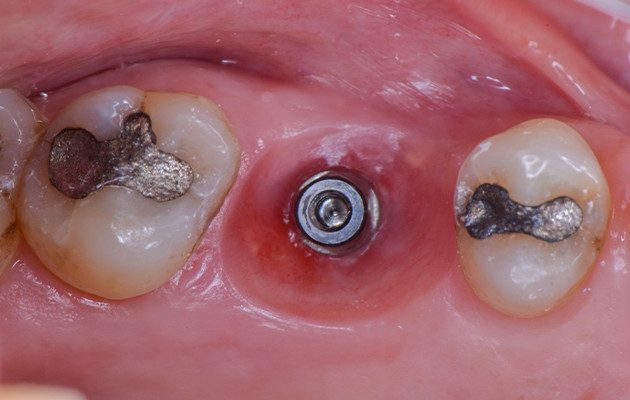

11 | Cicatrizador Multifuncional Arcsys posicionado sobre o implante.

12 | Resina composta fluida unida ao Cicatrizador se estendo até as margens do tecido mole para manter o contorno tecidual durante o período de osseointegração do Implante.